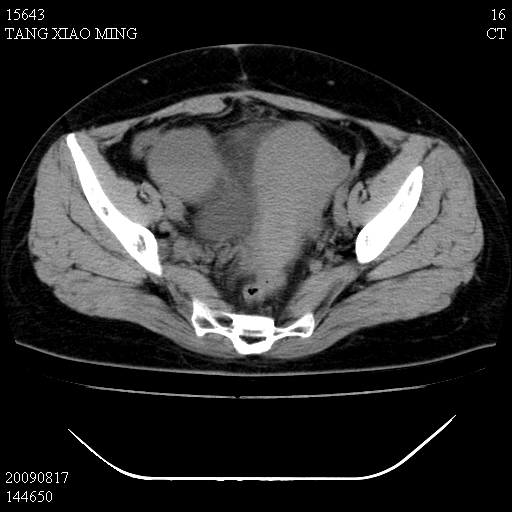

标题: CT21692:盆腔病变

女,33岁,右下腹痛2年余,既往宫外孕病史,如在我院手术,结果下周公布,

可能的诊断。1子宫内膜异位【子宫腺肌症并右卵巢巧克力囊肿】;2 右卵巢囊腺瘤。子宫肌瘤

1)考虑卵巢巧克力囊肿,不排除卵巢囊腺瘤。2)子宫肌瘤可能。

卵巢囊腺瘤,子宫肌瘤,直肠壁厚,不除外占位.